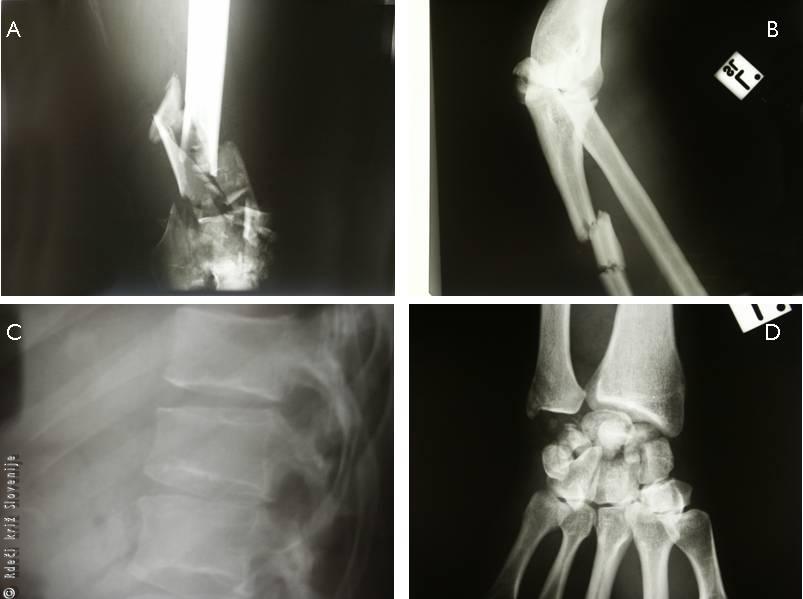

24-letni moški se je s prijateljem po večurnem veseljačenju in popivanju vračal iz praznovanja rojstnega dne. V nočnih urah je vozilo z neprilagojeno hitrostjo v nepreglednem ovinku na spolzki cesti zaneslo na nasprotni vozni pas. Vozilo je silovito trčilo v nasproti vozeč tovornjak. Sopotnika je vrglo iz vozila in je obležal mrtev na kraju dogodka. Voznik tovornjaka je bil lažje poškodovan in je takoj poklical 112 in policijo. Reševalci so v kratkem času prispeli na pomoč in poškodovanca izrezali iz vozila. Nudili so mu prvo pomoč, imobilizirali poškodovane ude, nudili podporno zdravljenje in ga takoj odpeljali v prostor za oživljanje večje bolnišnice. Pri začetnem pregledu je bilo ugotovljeno, da ima poškodovanec številne zlome: zdrobljeni zlom stegnenice nad kolenom, zlom nadlahtnice in koželjnice, dvojni zlom podlahtnice, zlom zapestnih kosti, zlom telesa ledvenega vretenca, številne udarnine in rane.

Slika 31

A – Zdrobljeni zlom stegnenice nad kolenom.

B – Dvojni zlom podlahtnice.

C – Zlom telesa ledvenega vretenca.

D – Zlom zapestnih kosti.

Po predhodni pripravi je bil premeščen v operacijsko dvorano, kjer so učvrstili zlome s ploščami in vijaki ter intramedularnim žebljem. Nato je bil premeščen v center za intenzivno terapijo. Kasneje je bil še večkrat operiran in potreboval je dolgotrajno razgibavanje in rehabilitacijo v zdravilišču. Kljub številnim operacijam, dragemu bolnišničnemu zdravljenju in dolgotrajnem razgibavanju poškodovanec brez opore ne more samostojno hoditi.